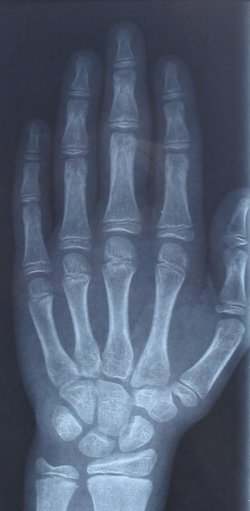

تتكون اليد البشرية من الكف متصل بها 5 أصابع مختلفة الأحجام ، وتتصل راحة اليد مع الذراع عن طريق الرسغ.[1][2]

العظام